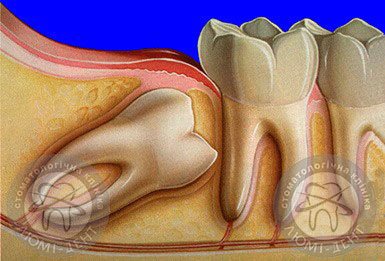

2) Горизонтальное – зуб изначально вырос в этом положении и продолжал рост, доставляя дискомфорт своим соседям. Здесь удаление необходимо для верхнего или нижнего зуба мудрости, но его будет сделать сложнее.

Сложности также возникают, если необходимо удаление моляра, растущего горизонтально. Он может вызывать ряд неприятных ощущений во время самого роста и после удаления. Такой зуб может годами беспокоить и пробиваться наружу постепенно, поэтому важно выявить его сразу и вовремя удалить.